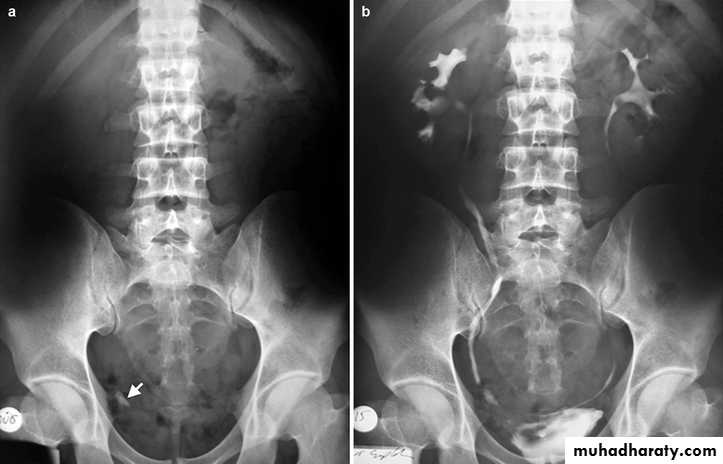

Urinary calculi

Assessment of acute ureteric colic

• Intravenous (Excretory) Urography